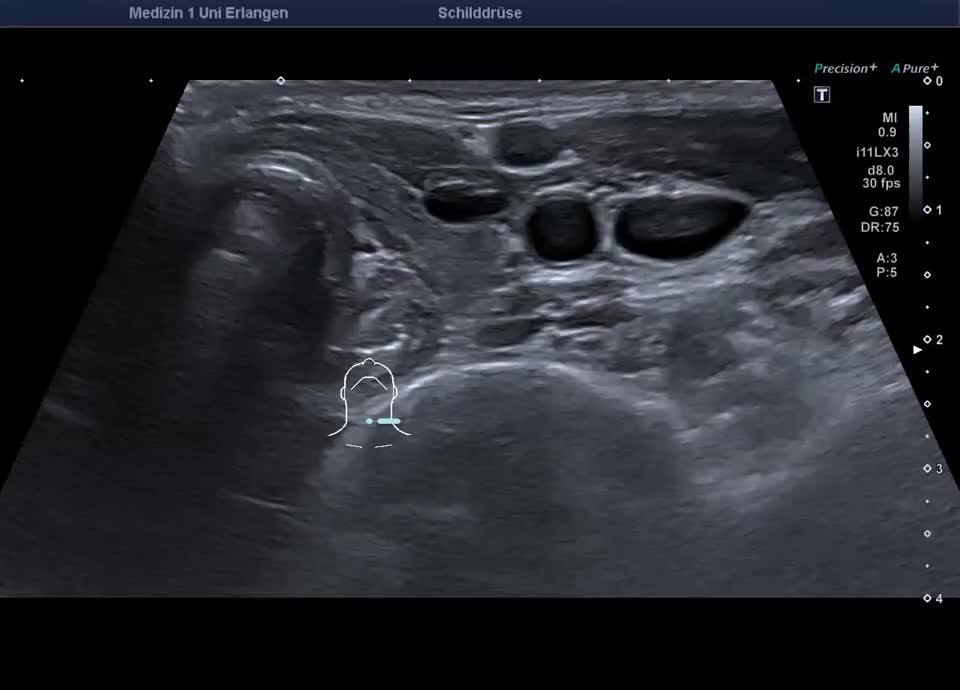

36-year-old patient with tremor, tachycardia, exophthalmos, and weight loss. Thyroid ultrasound shows bilaterally hypoechoic, inhomogeneous parenchyma with a total volume of 20.5 ml. Color Doppler sonography shows hypervascularization. Laboratory results: basal TSH decreased, T3/fT4 elevated, TRAK positive, consistent with Graves’ disease. Symptoms resolved under treatment with thiamazole and propranolol. At follow-up two years later, sonography showed a hyperechoic minimally inhomogeneous parenchyma with normal volume (15 ml).